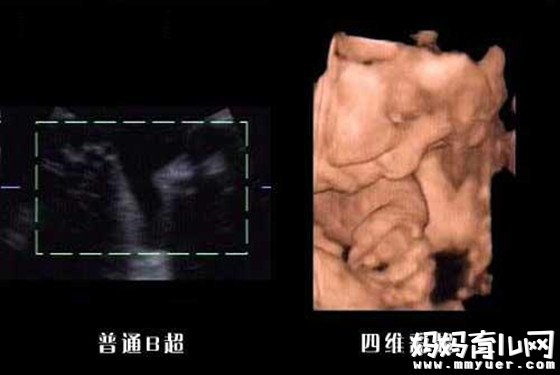

怀孕八个月男胎儿图

怀孕29周,这时胎儿体重大约有1300多克,坐高约为26-27厘米,如果加上腿长,身长大约已有43厘米了。这时胎儿的皮下脂肪已初步形成,看上去比原来显得胖一些了。手指甲也已很清晰。此时如果有光亮透过妈妈子宫壁照射进来,胎儿就会睁开眼睛并把头转向光源,这说明胎儿的视觉发育已相当完善。